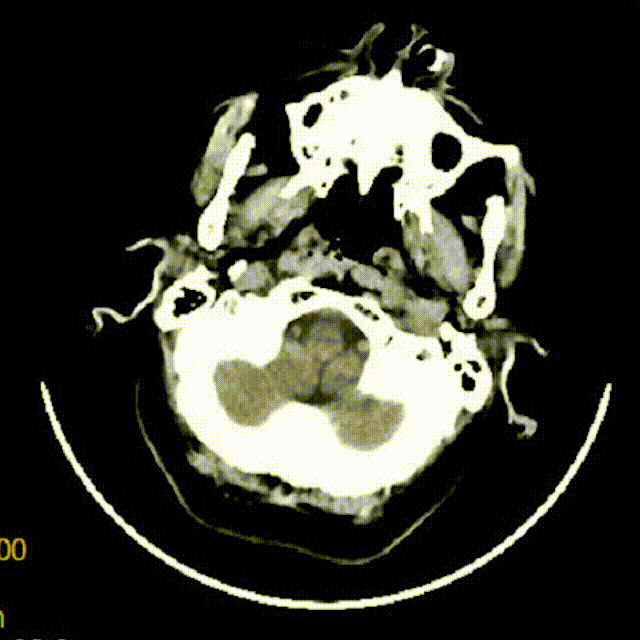

术前影像

1年前的MRA提示该部位重度狭窄。